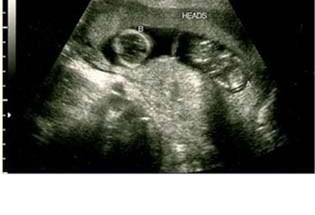

Gran revuelo causó la ecografía que se propagó por la red mostrando a dos bebés de una paciente llamada ‘Gómez, S’, avivando los rumores de que la Selena Gómez podría estar esperando gemelos de Justin Bieber.

Asimismo, en el informe que se difundió en las redes sociales se aseguró que la intérprete de ‘Come and get it’ acudió a una clínica para realizarse una serie de estudios médicos para descartar un posible embarazo.

La pagina web HollywoodLife confirmó que dicho documento es totalmente falso, y que Selena Gómez no espera a la cigüeña por ahora.